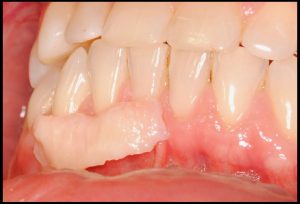

- Restablecer el LAC (límitite amelo cementario)

Fotografías del proceso: